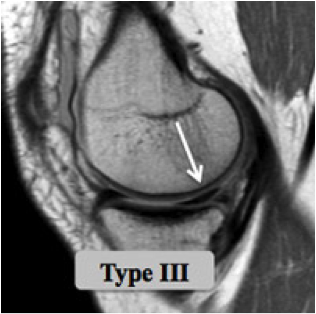

Des examens plus spécifiques comme l'IRM et l'arthroscanner sont demandés si les radiographies sont normales; ils vont permettre de visualiser les structures ménisco-ligamentaires et cartilagineuses de l'articulation.